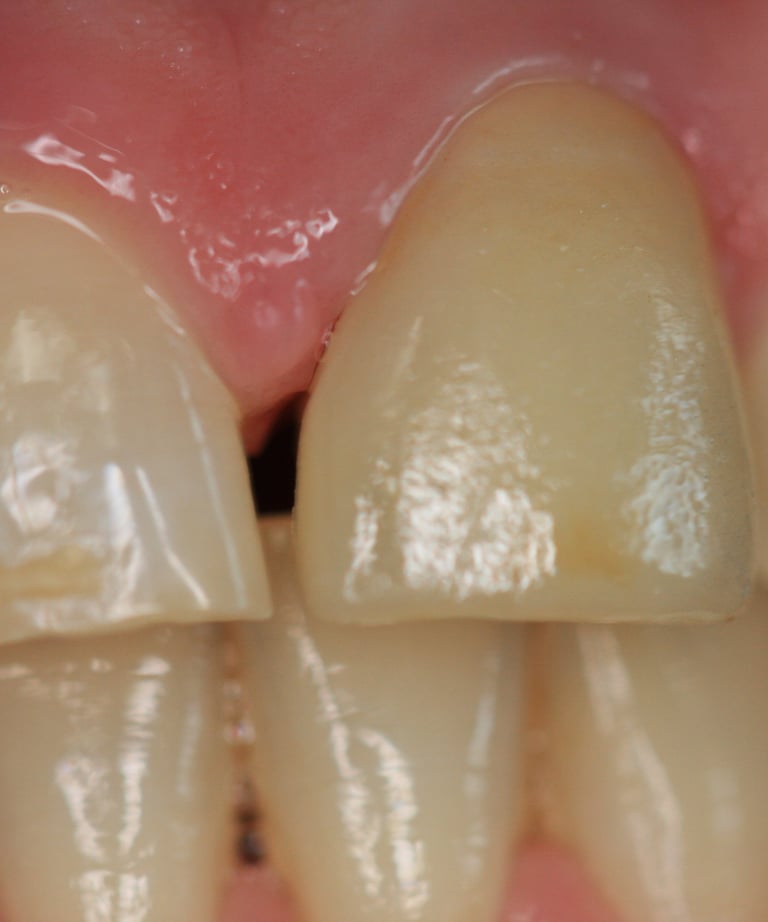

Il paziente si è presentato con una corona decementata ripetutamente sul dente 21, con un'evidente discrepanza estetica rispetto ai denti naturali adiacenti. L’elemento non si armonizzava con i tessuti circostanti e presentava problemi sia funzionali che estetici. Dopo una valutazione clinica approfondita, sono emersi i seguenti problemi:

Corona incongrua: Esteticamente non soddisfacente e incapace di mimetizzarsi con i denti naturali vicini.

Corona visibilmente discromica rispetto ai denti naturali.

Decementazione frequente della corona.